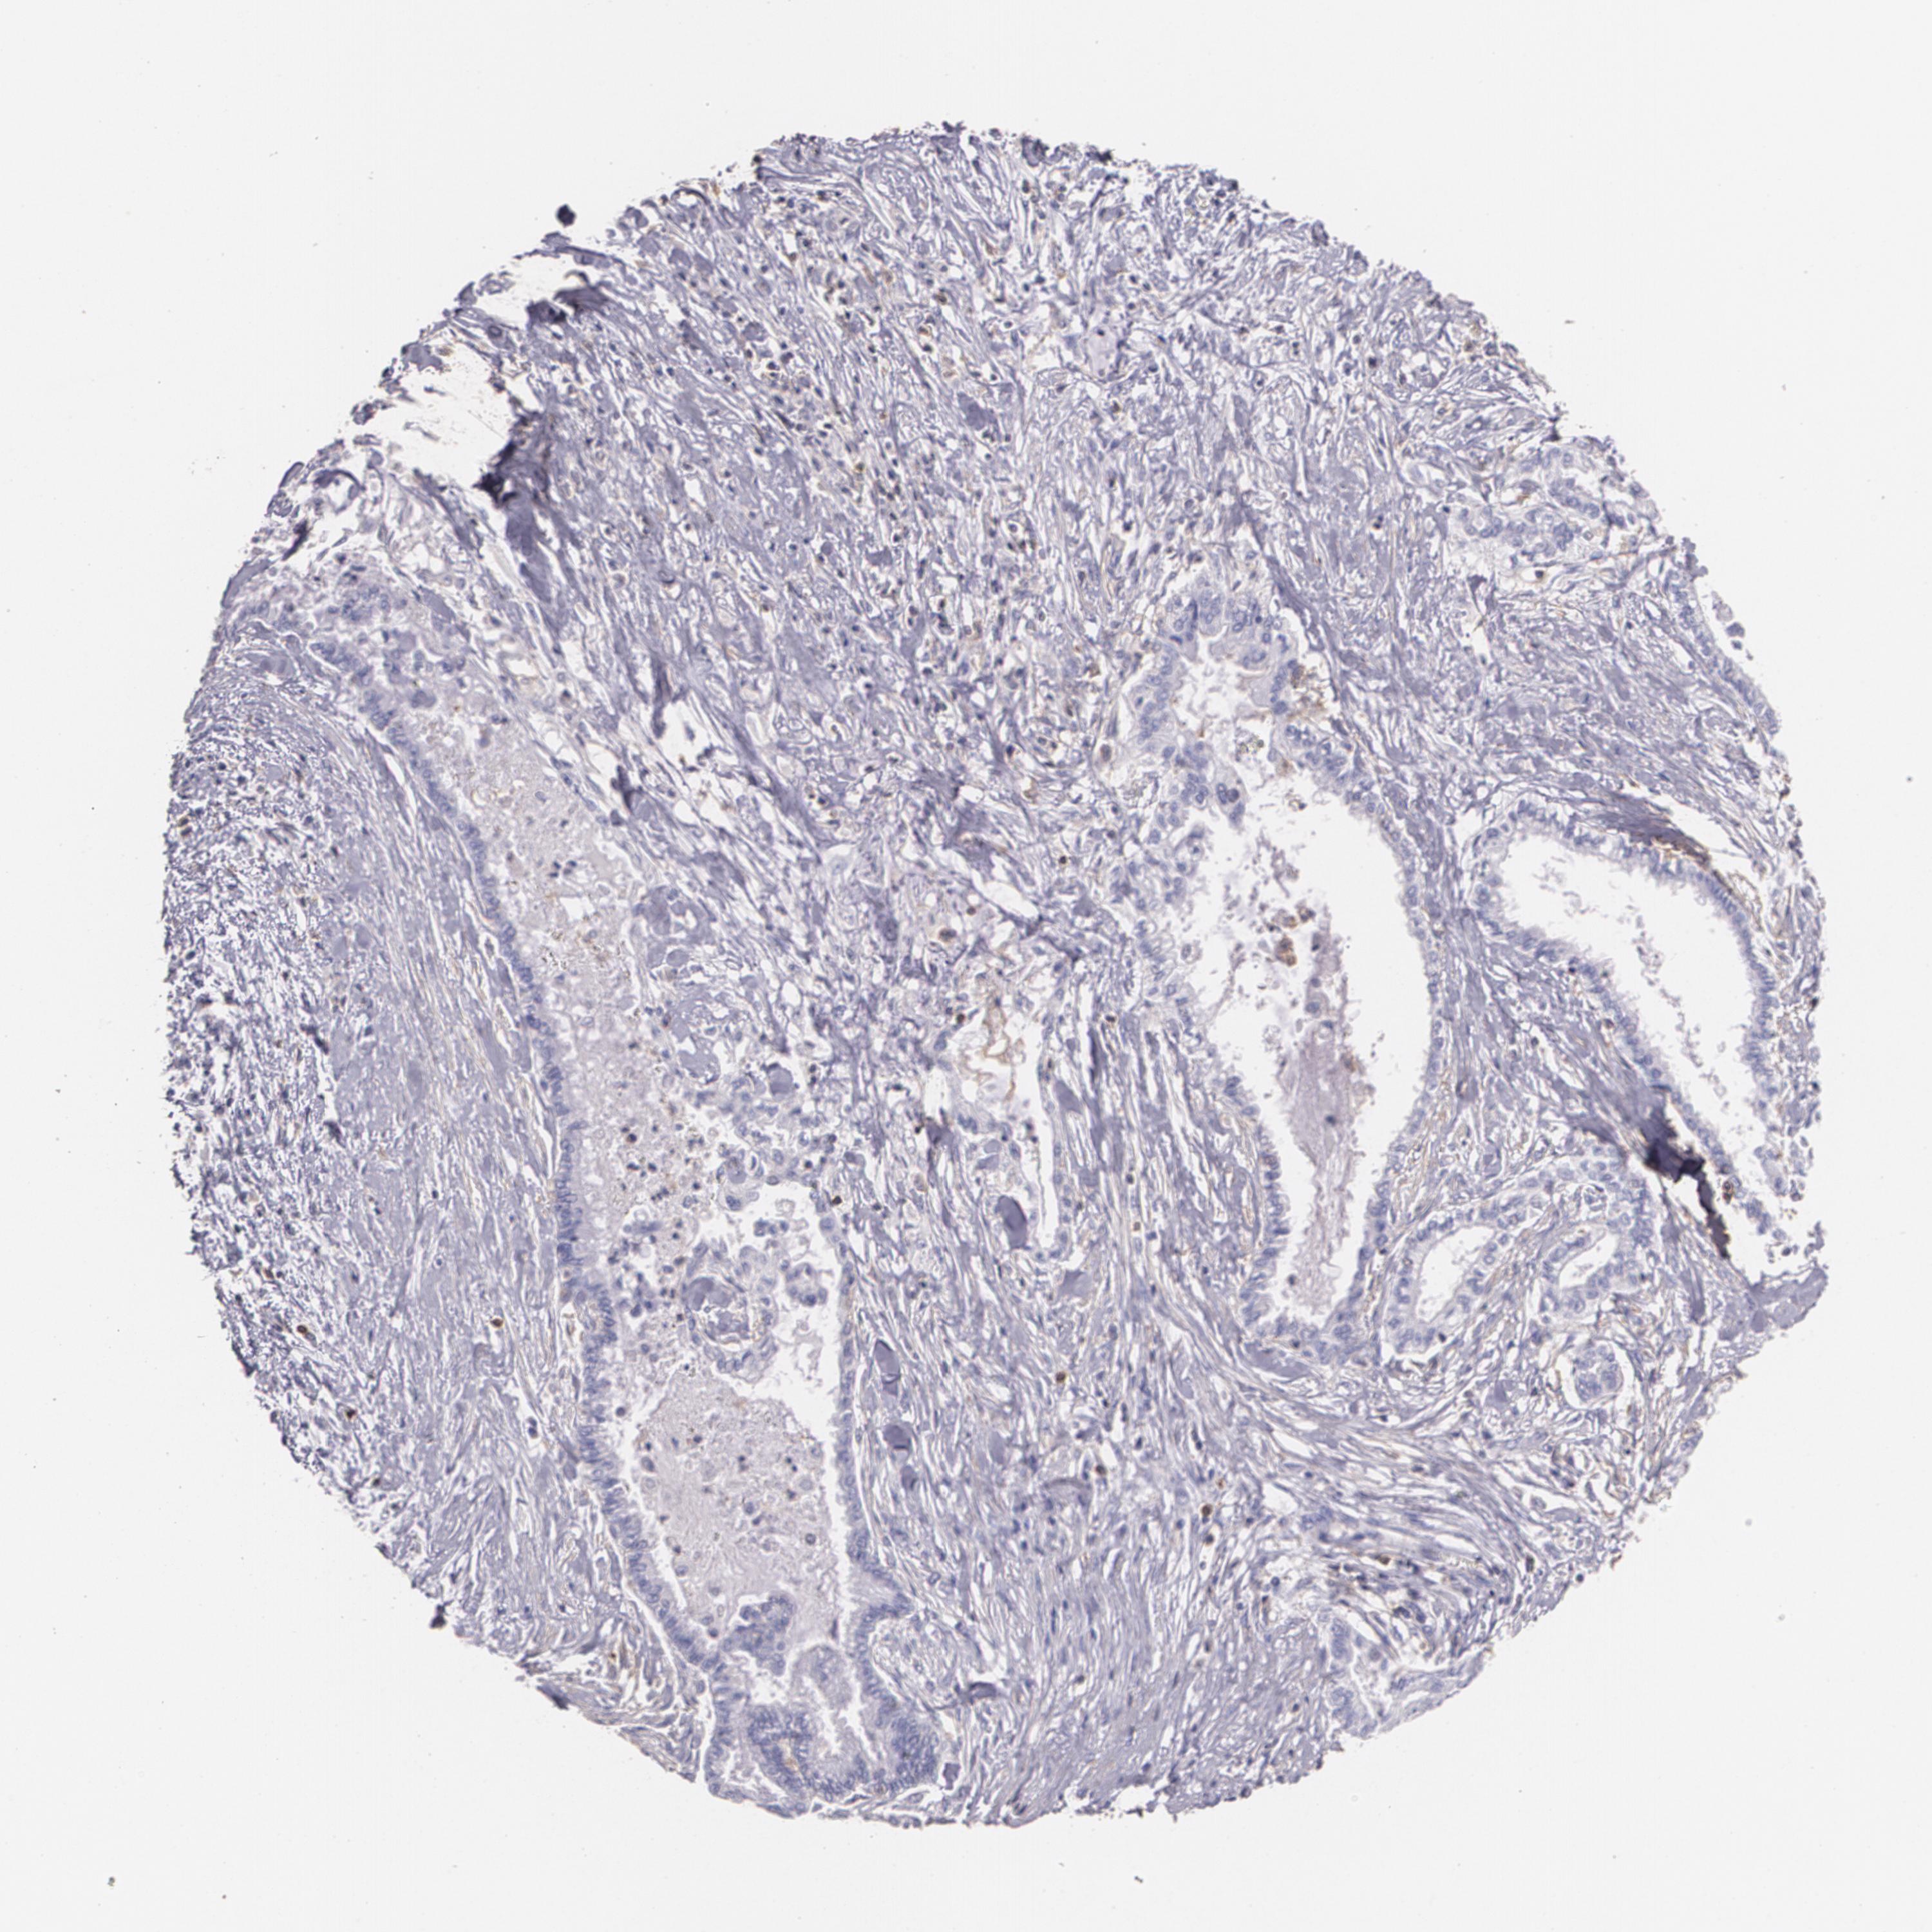

PANCREATIC CANCER - Protein expressioni

A mouse-over function shows sample information and annotation data. Click on an image to view it in a full screen mode. Samples can be filtered based on level of antibody staining by selecting one or several of the following categories: high, medium, low and not detected. The assay and annotation is described here.

Note that samples used for immunohistochemistry by the Human Protein Atlas do not correspond to samples in the TCGA dataset.

Antibody stainingi

Antibody staining in the annotated cell types in the current human tissue is reported as not detected, low, medium, or high, based on conventional immunohistochemistry profiling in selected tissues. This score is based on the combination of the staining intensity and fraction of stained cells.

Each image is clickable and will lead to virtual microscopy that enables deeper exploration of all samples and also displays staining intensity scores, fraction scores and subcellular localization as well as patient and tissue information for each sample.

Antibody CAB002441

Antibody CAB031481

Staining

High

Medium

Low

Not detected

Intensity

Strong

Moderate

Weak

Negative

Quantity

>75%

75%-25%

<25%

None

Location

Nuclear

Cytoplasmic/membranous

Cytoplasmic/membranous,nuclear

Adenocarcinoma, NOS

Adenocarcinoma, metastatic, NOS